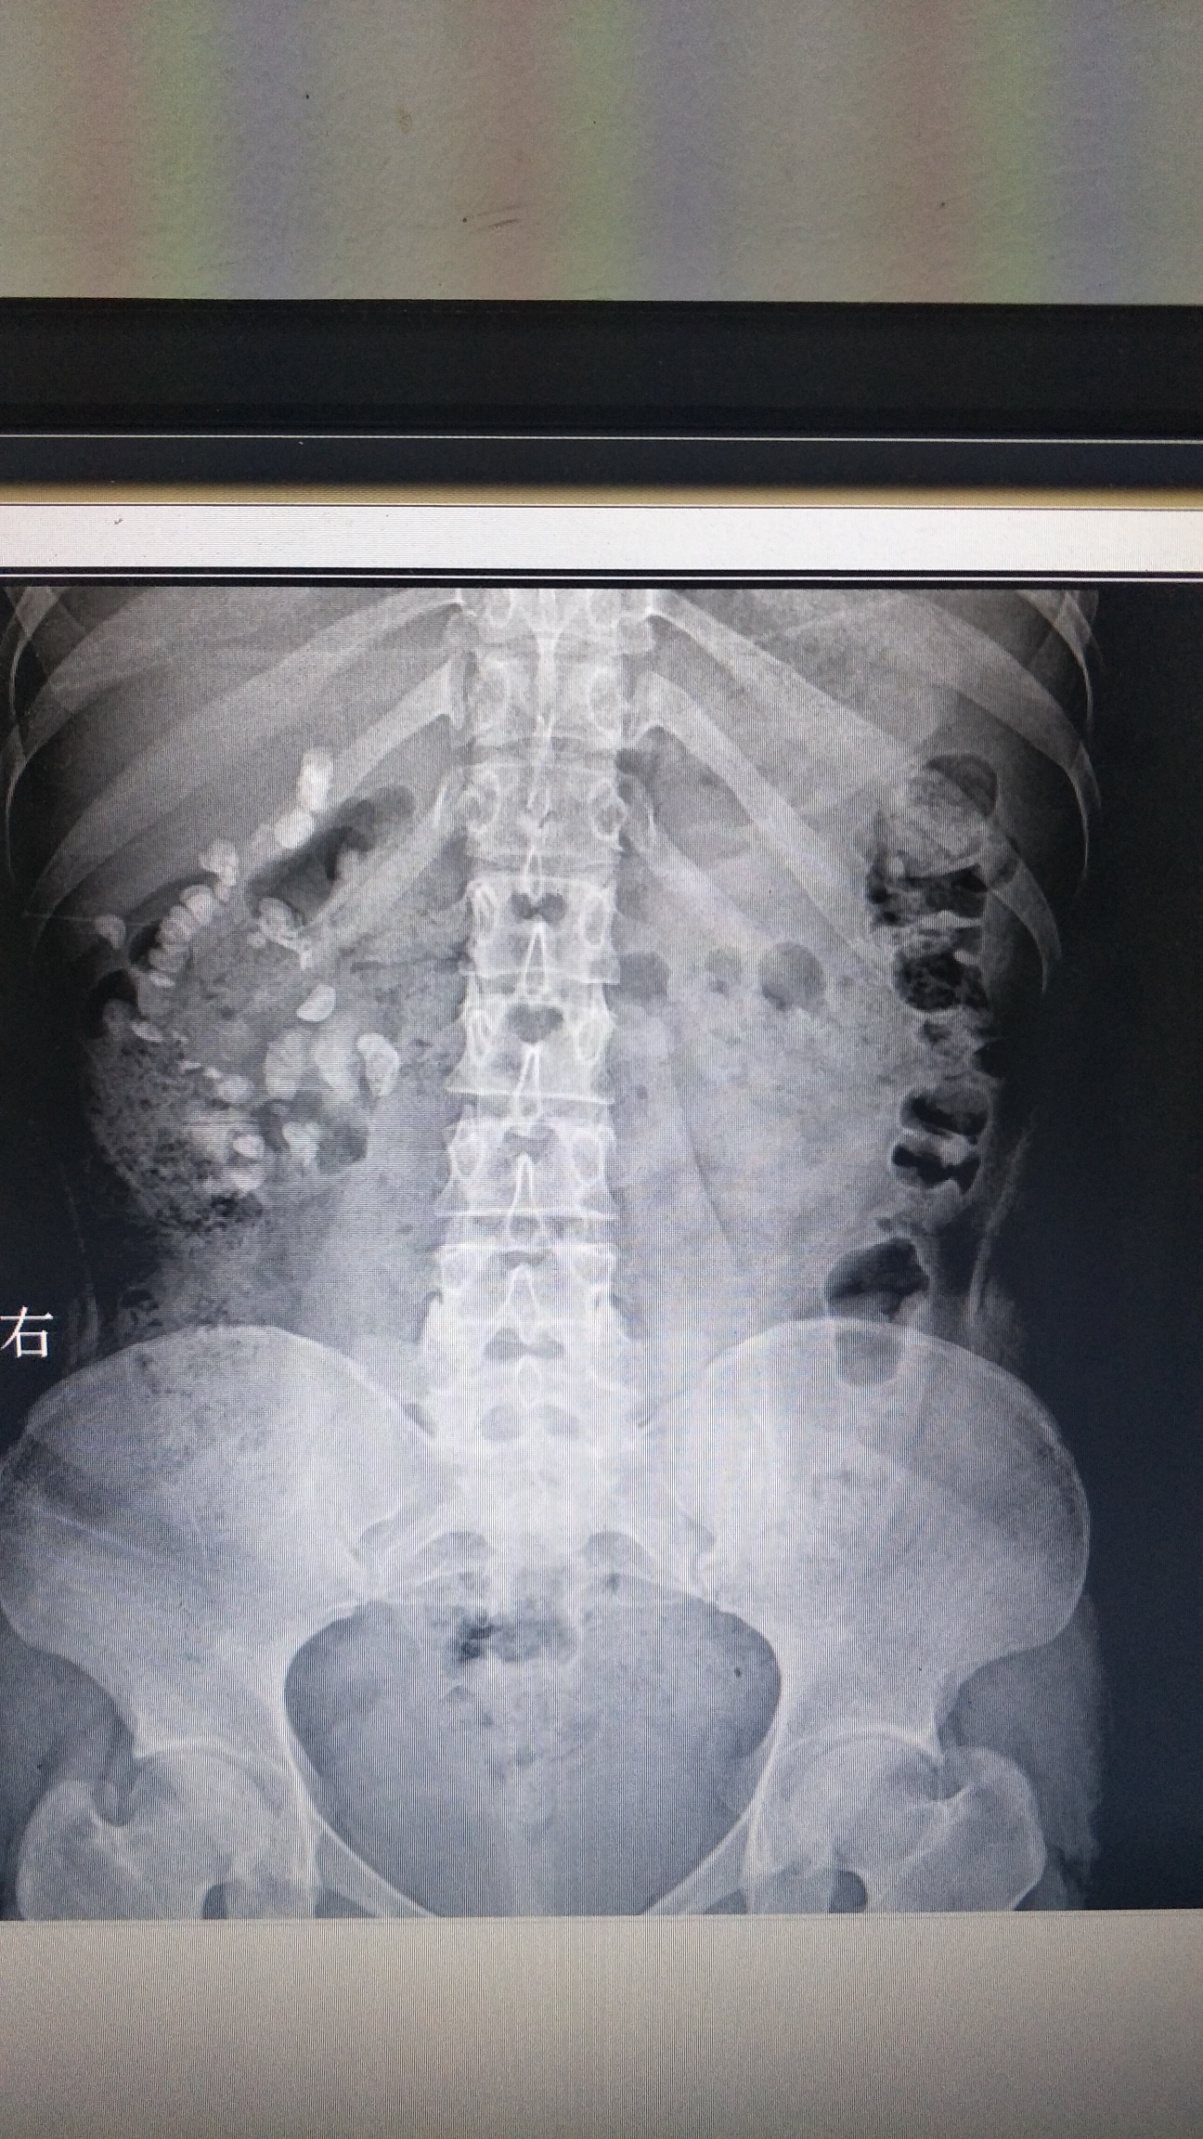

患者:王嬌,女性,21歲。因“體檢發(fā)現(xiàn)右腎結(jié)石8月余”入院,診斷為右腎多發(fā)結(jié)石、右輸尿管結(jié)石、右腎積水。于2019-07-17在全麻下行“輸尿管軟鏡聯(lián)合經(jīng)皮腎鏡右腎結(jié)石碎石取石術(shù)”, 此術(shù)式采取側(cè)仰臥奔跑位,為我科首次采用輸尿管軟鏡聯(lián)合經(jīng)皮腎鏡處理復(fù)雜性腎結(jié)石。優(yōu)點(diǎn)為軟性輸尿管鏡可以觀察和處理經(jīng)皮腎鏡不能達(dá)到的腎盂、腎盞內(nèi)的結(jié)石,配合鈥激光碎石效果滿意。對(duì)于腎臟復(fù)雜性結(jié)石清除率較高,效果良好,術(shù)后恢復(fù)快,5天后康復(fù)出院,對(duì)治療表示滿意。